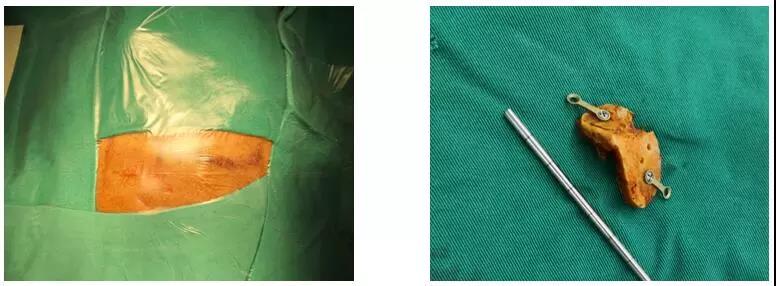

術(shù)中切口及骨瓣

據(jù)悉,按照以往的手術(shù)方式,賴先生需要在額顳部開一個長達15-20厘米左右的切口。手術(shù)創(chuàng)傷和風險大,且住院時間長,花費高。如今,惠州三院神經(jīng)外科開展了眉弓鎖孔入路這項技術(shù),只需在眉弓上緣開一長約5厘米左右的切口就能完全夾閉動脈瘤。既完整切除了病灶,又避免了普通開顱手術(shù)對患者外觀與容貌的影響。

它根據(jù)每個患者的具體情況,準確設計開顱部位和范圍,充分利用腦組織的自然間隙,以最短的手術(shù)路徑精確到達病變,將手術(shù)創(chuàng)傷降至最低。然而,這項技術(shù)對術(shù)者的要求很高,必須具備扎實的神經(jīng)解剖生理基礎和精湛的顯微手術(shù)基本功。